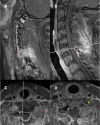

Figure 2. MRI cervical with and without contrast further characterizing mass

(A) Left parasagittal cervical MRI with contrast demonstrating heterogeneously enhancing mass (red arrows) originating from the facets with extension into the soft tissues of the neck. (B) Sagittal MRI with contrast demonstrating extradural mass of the posterior elements with extension into the soft tissues. (C) Axial MRI with contrast at the level of C6 shows mass involvement with the left facet and abuttal of the left vertebral artery. (D) Axial MRI with contrast at the level of C7 showing mass involvement of the left facet and abuttal with possible encasement of the left vertebral artery (yellow arrow) MRI: magnetic resonance imaging